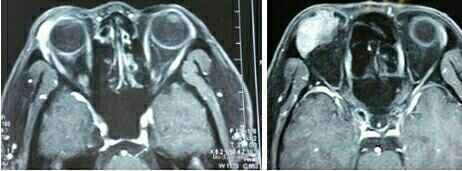

查体:全身检查无异常。眼部查体:视力 Vod: 0.8,Vos:0.6、眼压Tn,v双眼正位,无突出。右眼眼球向下方移位,向上方运动受限。双眼眶压Tn,右眼鼻侧眶上缘可触及肿物,边界清,2*1cm,可活动,质地中等,表面呈结节,无波动感。右眼结膜充血水肿,角膜透明,前房深,晶体透明。 超声:右眼眶实质性占位性病变声像(中低回声光团,边界欠清,形态不规则)。右眼上直肌肥厚声像。 左眼各眼外肌未见肥厚声像,左眼眶内未见明显占位性病变声像。 MRI:右侧泪腺增大,大小约1.6*2.9cm,边缘尚清,形态不规则T1W等信号,T2W为等及略低信号。压脂序列为稍高信号,增强扫描病灶中度强化,强化不均匀肿块不规则,未见包膜。局部眶壁未见骨质破坏。眼球等圆,边缘光滑。